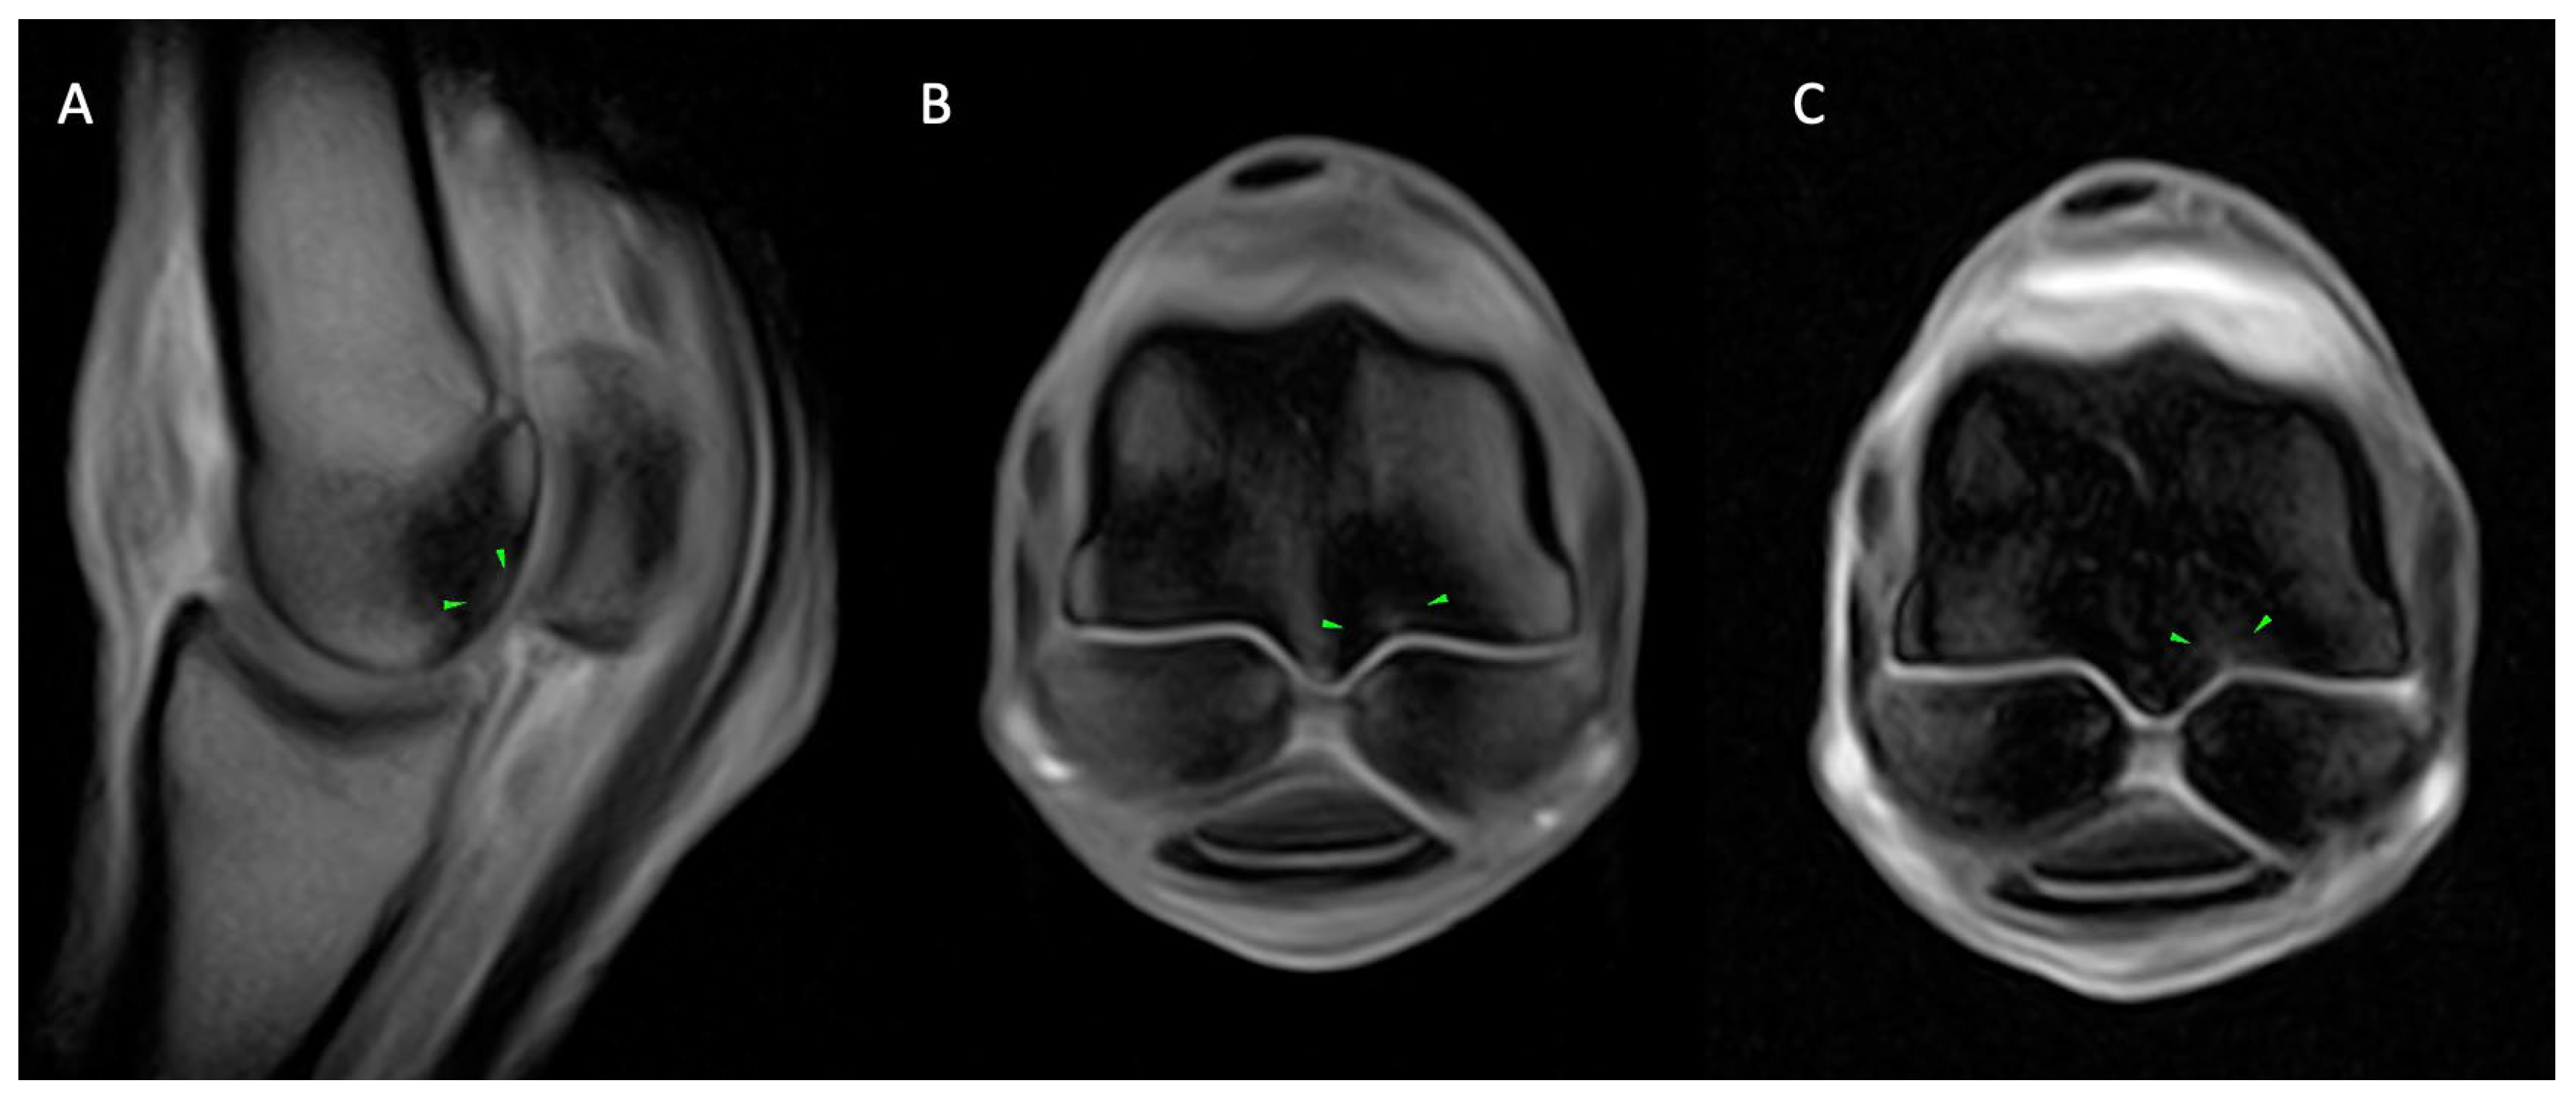

3.2.1. Osseous Pathology

3.2.2. Joint Pathology

3.2.3. Soft Tissue Pathology